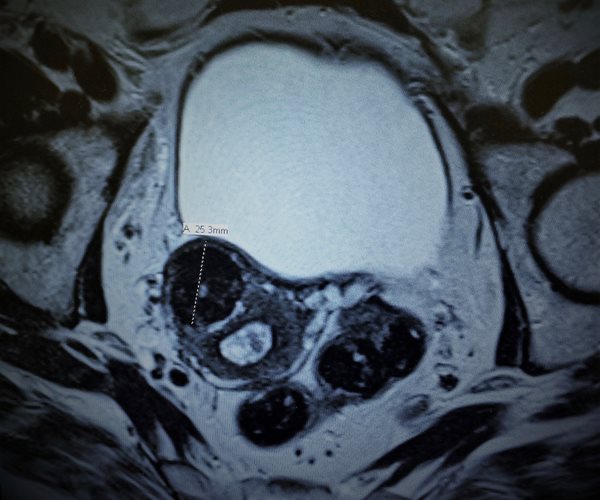

Uterine fibroids are muscular tumors that develop in the wall of the uterus, according to the U.S. Office on Women's Health (OWH). They're usually not cancerous and often don't cause any symptoms. If symptoms do occur, they may include heavy bleeding, frequent urination and pain during sex. Fibroids have also rarely been linked to infertility.

Women who don't want to have a hysterectomy have several other treatment options, including UFE. UFE involves threading a thin tube into the blood vessel that supplies blood to the fibroid. Small plastic or gel particles are injected into the blood vessel to block it, which causes the fibroid to shrink, the OWH said.